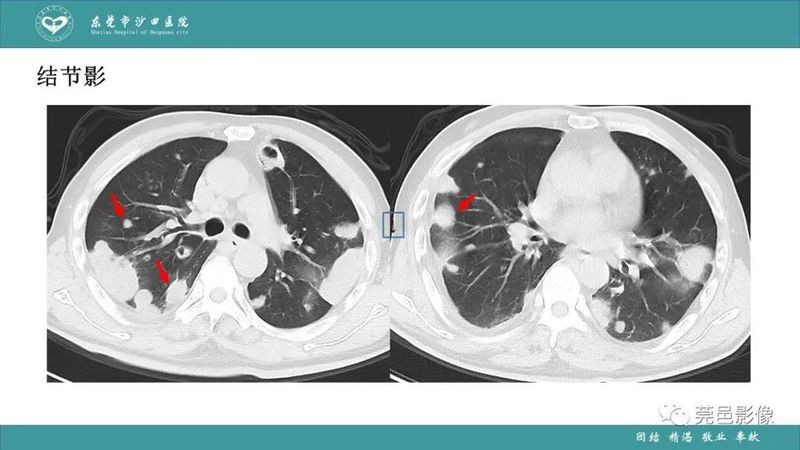

「肺炎克雷伯杆菌肺炎」影像学诊断+鉴别诊断